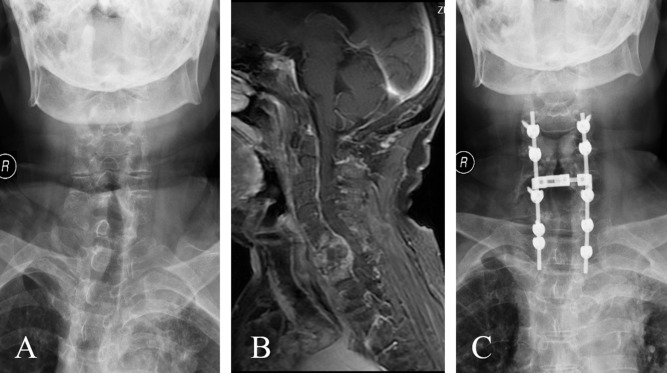

Декомпрессия позвонков

Декомпрессия позвонков 110 фото